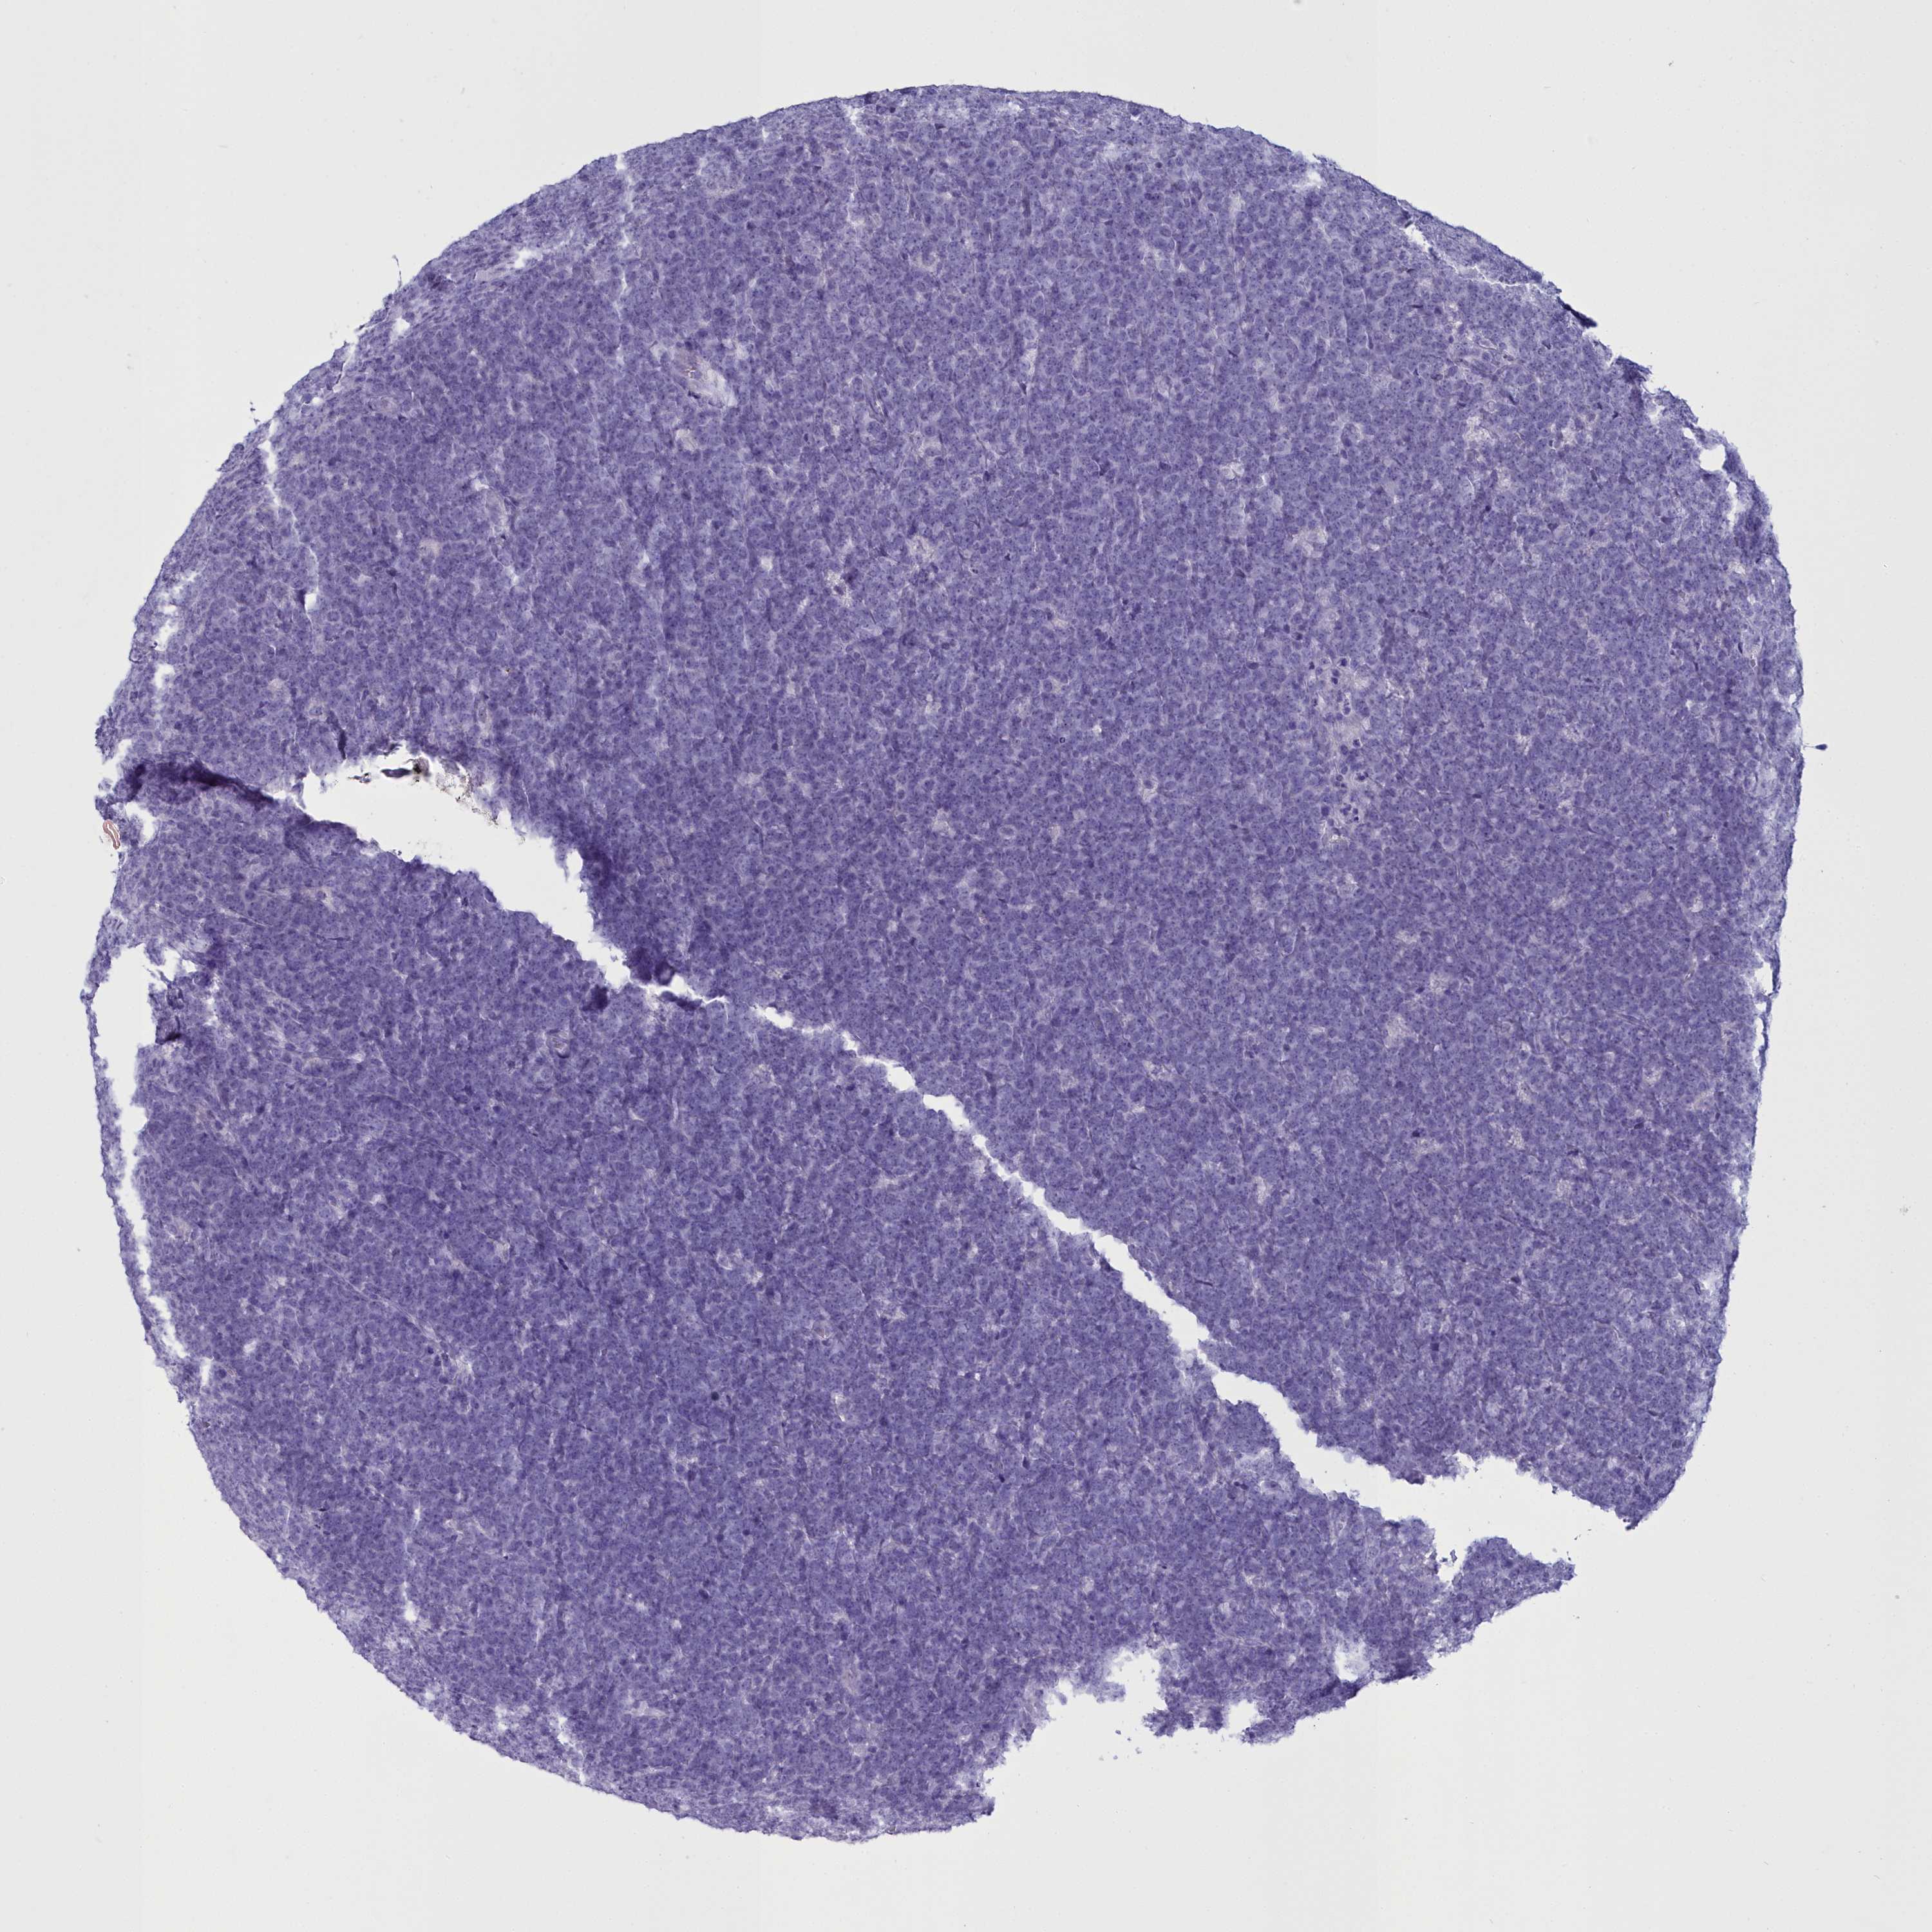

CANCER LYMPHOMA Show tissue menu

LYMPHOMA - Protein expressioni

A mouse-over function shows sample information and annotation data. Click on an image to view it in a full screen mode. Samples can be filtered based on level of antibody staining by selecting one or several of the following categories: high, medium, low and not detected. The assay and annotation is described here.

Each image is clickable and will lead to virtual microscopy that enables deeper exploration of all samples and also displays staining intensity scores, fraction scores and subcellular localization as well as patient and tissue information for each sample.

Antibody HPA039061

Antibody HPA039062

Antibody CAB015442

Antibody CAB022600

Hodgkin's disease, NOS

Malignant lymphoma, non-Hodgkin's type, High grade

Malignant lymphoma, non-Hodgkin's type, Low grade